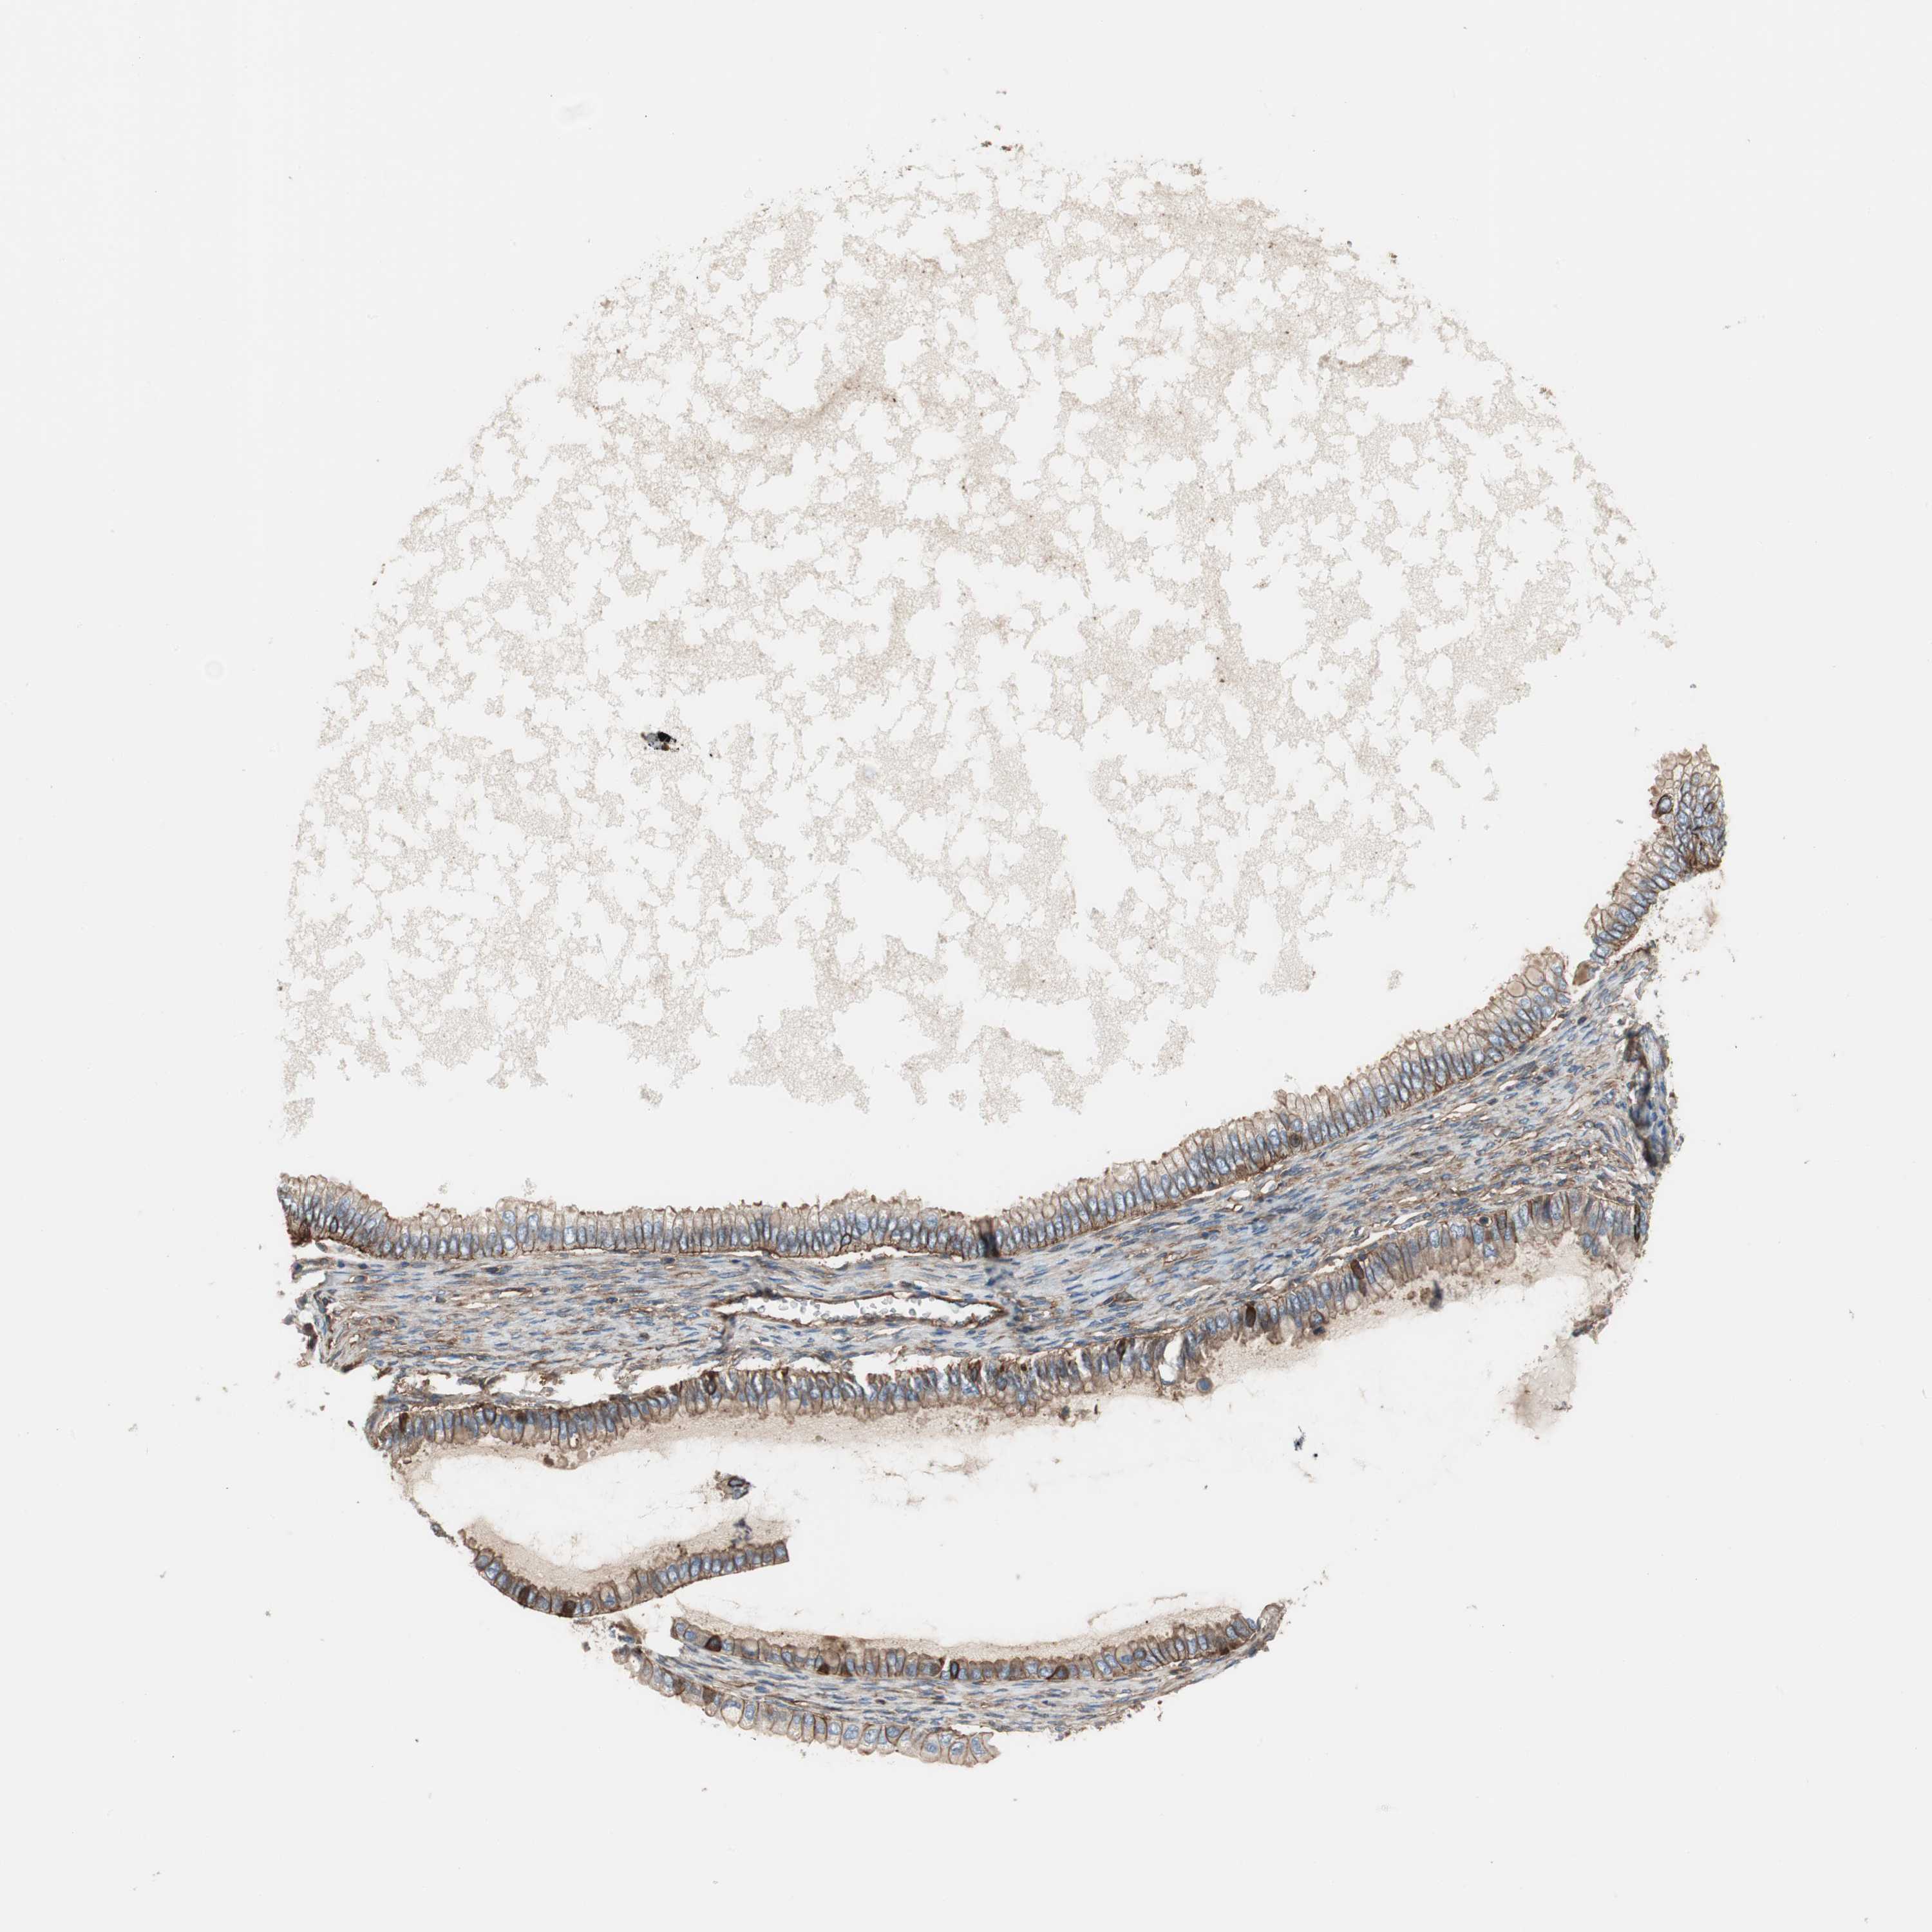

OVARIAN CANCER - Protein expressioni

A mouse-over function shows sample information and annotation data. Click on an image to view it in a full screen mode. Samples can be filtered based on level of antibody staining by selecting one or several of the following categories: high, medium, low and not detected. The assay and annotation is described here.

Note that samples used for immunohistochemistry by the Human Protein Atlas do not correspond to samples in the TCGA dataset.

Antibody stainingi

Antibody staining in the annotated cell types in the current human tissue is reported as not detected, low, medium, or high, based on conventional immunohistochemistry profiling in selected tissues. This score is based on the combination of the staining intensity and fraction of stained cells.

Each image is clickable and will lead to virtual microscopy that enables deeper exploration of all samples and also displays staining intensity scores, fraction scores and subcellular localization as well as patient and tissue information for each sample.

Antibody HPA007406

Antibody HPA007917

Cystadenocarcinoma, serous, NOS

Carcinoma, endometroid

Cystadenocarcinoma, mucinous, NOS

Carcinoma, NOS